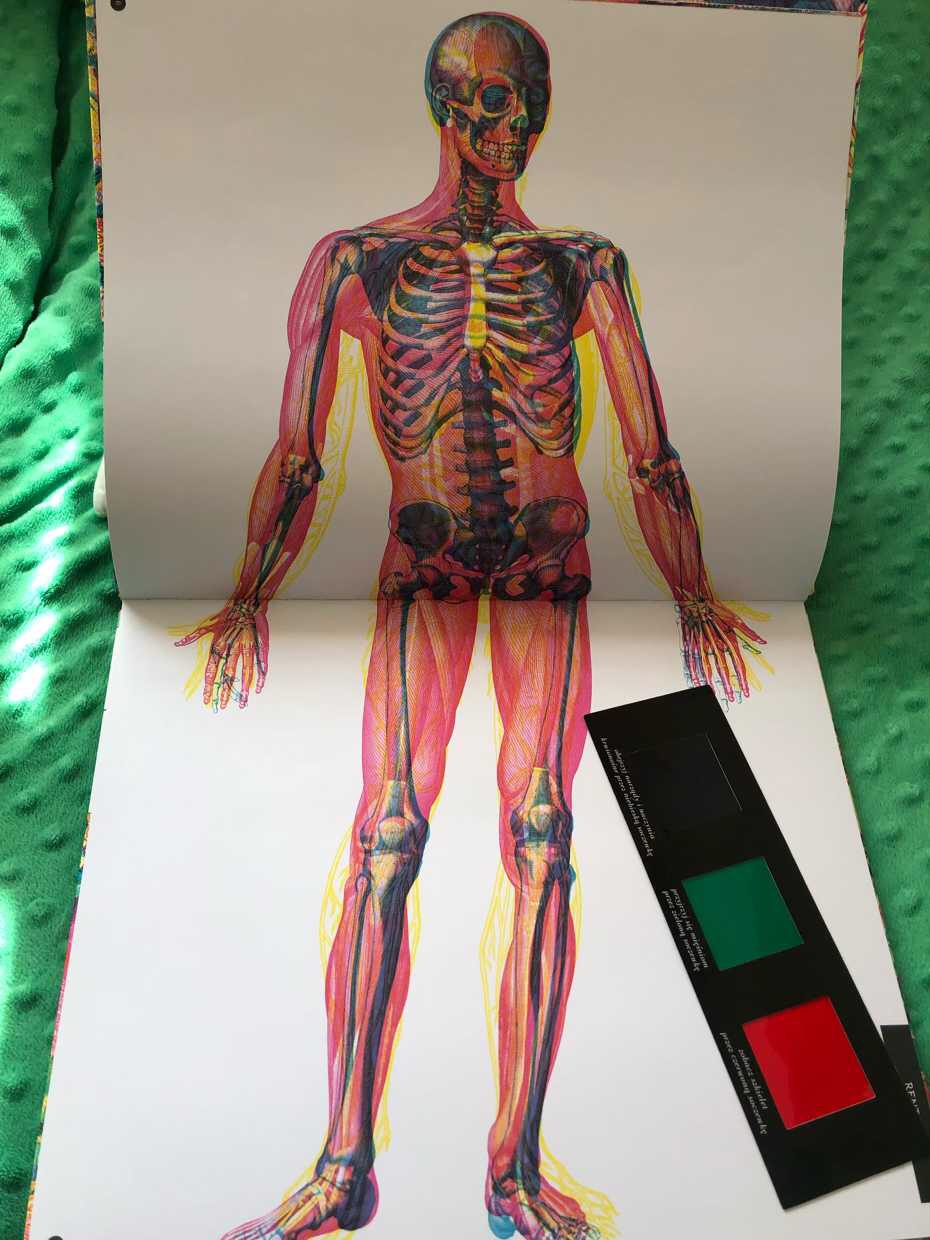

Ilustracje mogą wyglądać na nieco pomieszane przez różowe, żółte i zielone obrazy oraz linie, które wydają się skomplikowane do odczytania. Jednak przeglądanie książki za pomocą soczewek zamienia to, co było nieostre, w coś wyraźnego i pouczającego.

System filtrów staje się czymś znacznie więcej niż sztuczką, to czyni książkę wyjątkowym doświadczeniem. Kiedy zamieniamy kolory, widzimy niesamowity efekt odsłaniający szkielet pod ciałem i mięśniami.

Patrząc przez czerwony czytnik soczewki, odkrywamy szkielet ciała, zielona soczewka odkrywa mięśnie, a niebieska pokazuje narządy i naczynia krwionośne. Zauważyłam, że używając niebieskiej soczewki, obrazy są dość ciemne. Trzeba mocno wytężyć wzrok, aby coś dostrzec.

W jednej części książki opisano, jak rośnie dziecko, w tym podano informacje o narządach rozrodczych, wraz ze schematem organów wewnętrznych bez obrysu ciała. W tym temacie, gdy czytelnicy używają kolorowych soczewek w rentgenie, mogą zobaczyć szkielet, mięśnie brzucha i dziecko. Adaś zafascynował się płodem i z tego tytułu miał wiele pytań. Długo analizował rozwój dziecka i jego ułożenie.